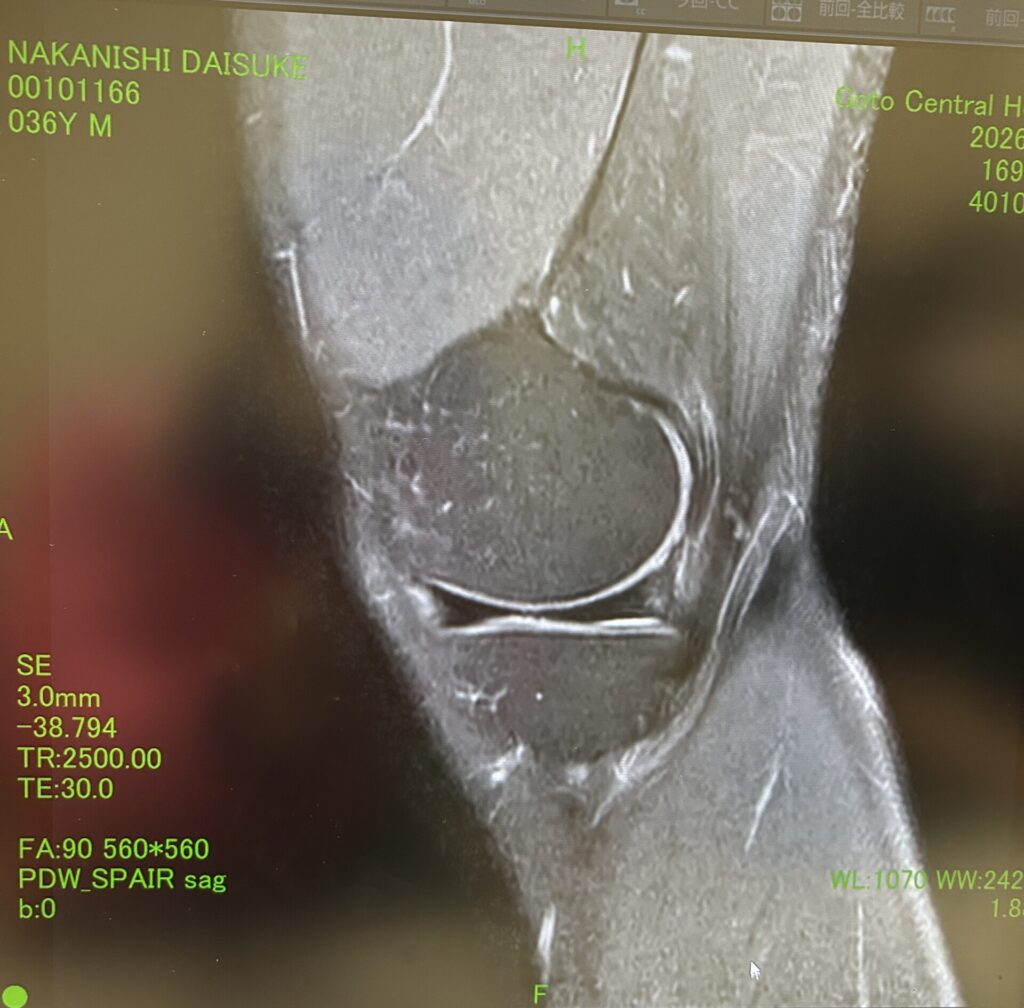

最初はランナー膝かなと思っていましたが、中々回復が遅かったので1月に五島病院でMRIを取って頂きました。

その結果、円盤状半月板という事が分かりました。